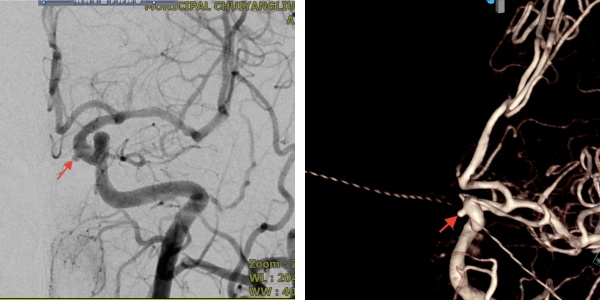

近日,清华大学附属垂杨柳医院神经内科成功为一名63岁女性患者拆除了脑内的“不定时炸弹”。该患者在住院期间通过脑血管检查,发现左侧颈内动脉C4段存在一枚动脉瘤。经综合评估,该动脉瘤破裂风险较高。

▲术前DSA

经与家属充分沟通同意后,医院神经内科副主任医师胡益民、苏杭完成颅内动脉瘤密网支架植入术。手术效果良好,有效避免了日后动脉瘤破裂的风险,也为颅内动脉瘤患者提供了更微创的治疗选择。今天,我们就借这个案例,带大家了解一下这项脑动脉瘤治疗技术:密网支架植入手术。

为精准把握手术指征与安全,术前,需完善全脑血管造影对动脉瘤的形态、大小及载瘤动脉的血管条件进行全面评估;术中,需由经验丰富的神经介入医生精准将密网支架植入病变部位;术后,患者需严格遵医嘱服用抗血小板药物,以预防支架内血栓形成及缺血性卒中事件的发生,并需定期复查全脑血管造影,以评估动脉瘤的最终闭塞情况。本例患者行密网支架植入术后三个月复查全脑血管造影,结果显示密网支架贴壁良好,无支架内血栓形成,继续用药和定期复查即可。